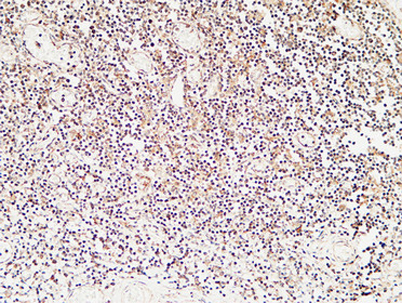

Calcitonin rabbit pAb

Product name: Calcitonin rabbit pAb

Dilutions: IHC-p: 100-300.WB 1:500-2000, ELISA 1:10000-20000

Immunogen: Synthetic peptide from human protein at AA range: 80-141